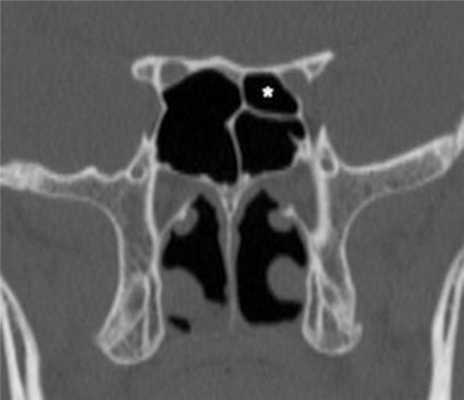

(Слева) На сагиттальной КЛКТ (реконструкций) визуализируется большое куполообразное объемное образование без кортикальной пластинки с плотностью мягких тканей (гиперденсное относительно воздуха), сопоставимое с муцинозной ретенционной псевдокистой верхнечелюстной пазухи. Край пазухи возле кисты интактен.

(Справа) На аксиальной КЛКТ (реконструкция) визуализируется муцинозная ретенционная псевдокиста, занимающая всю камеру правой верхнечелюстной пазухи на этом уровне. Важно не спутать перегородку в пазухе с кортикальной пластинкой на периферии образования. Обратите внимание на утолщение слизистой оболочки камер левой верхнечелюстной пазухи.